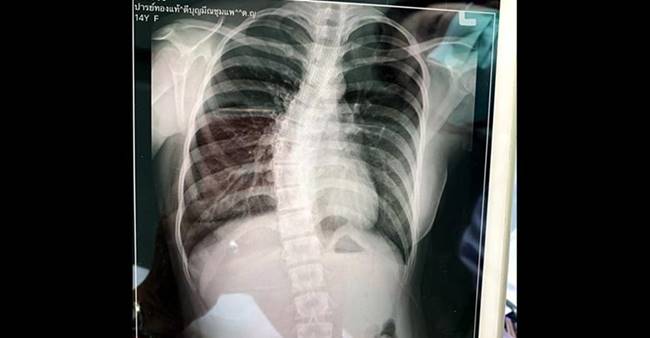

ลูกสาวมีอาการกระดูกสันหลังคดงอ โดยมีภาพเอกซเรย์จากทีมแพทย์มายืนยัน

พร้อมกับนำภาพเอกซเรย์ที่พบกระดูกสันหลังคดงอ